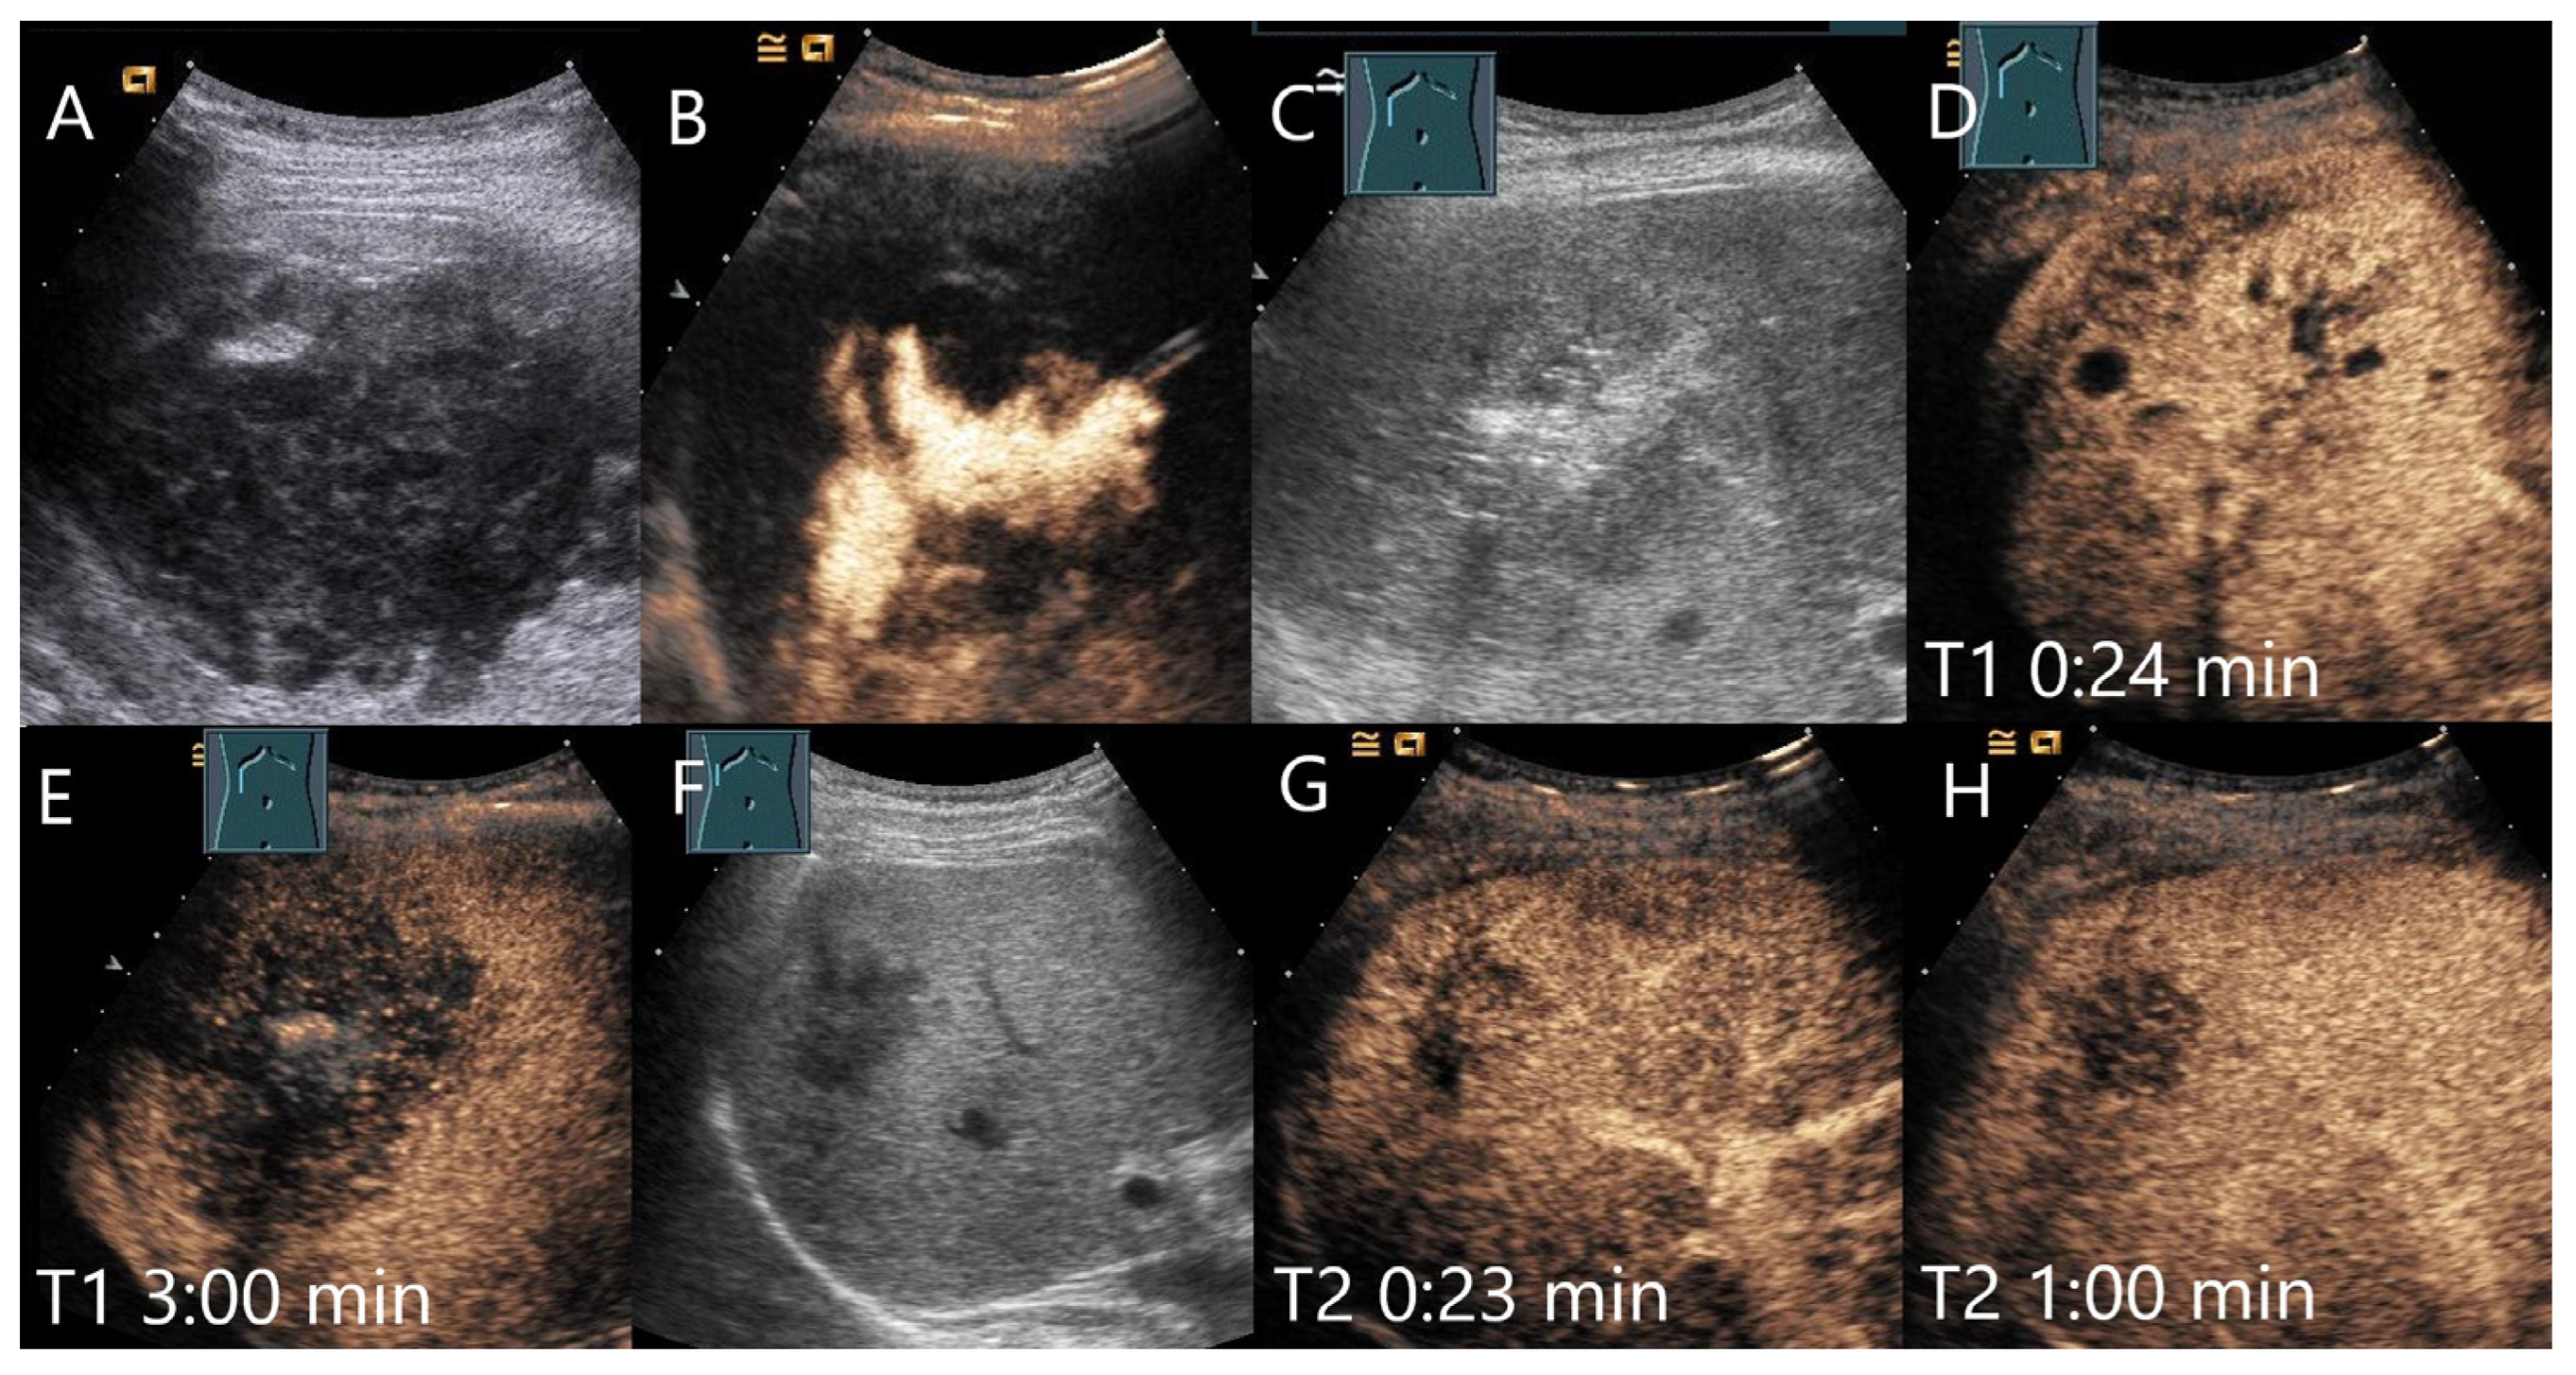

Amebic abscesses have a similar appearance in B-mode US [88]. We are only aware of one case report describing an amoebic abscess in the CEUS [89]. An amebic abscess on B-mode US and CEUS is shown in Figure 12.

Figure 12.

Female patient with amebic abscess, fever, and general malaise after a stay in northern India. On B-mode US, a 90 × 65 mm large liquid hypoechoic, well demarcated FLL (A). The abscess was relieved by drainage and the position was checked by intracavitary CEUS (B). After complete drainage of the liquid contents, a hypoechoic lesion remained (C). The liver tissue surrounding the heterogeneous enhanced lesion showed a large area of arterial isoenhancement after 24 s (D). The lesion is hypoenhanced after 3 min with hyperenhanced surrounded parenchyma (E). Serology revealed an elevated amebic titer. Under appropriate therapy, regression occurred after 4 weeks (F). However, the lesion showed a hypoenhancement after 23 s (G) and progressive washout after 1 min (H).